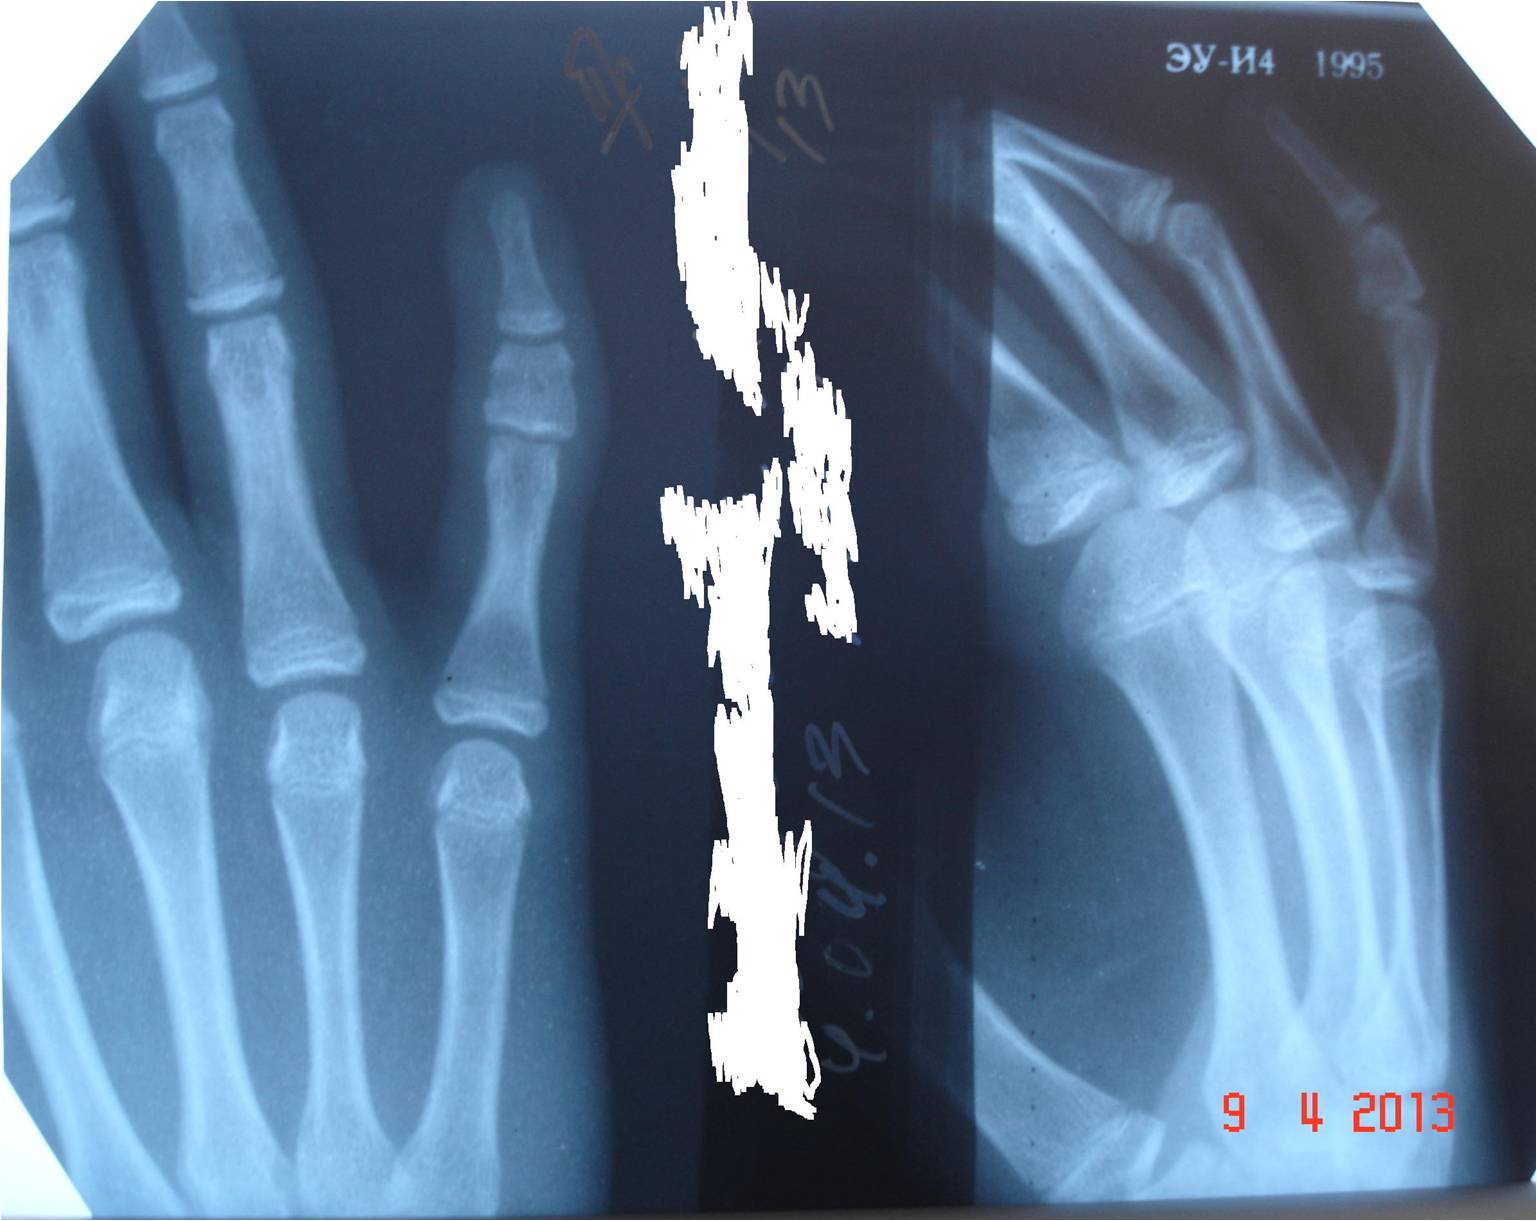

Девочка, 13 лет. Обратилась с жалобами на деформацию V пальца левой кисти. Замечать стала около 1 месяца назад. Травму отрицает. Занимается в музыкальной школе 6 лет (фортепьяно). Клинически: варусная деформация и относительное увеличение в объеме V пальца левой кисти (объем V пальцев D<S). Функция V пальца левой кисти сохранена. Выполнена сравнительная рентгенография V пальцев обеих кистей.

Да, клинодактилия. На фоне брахифалангии, надо думать.

Аномалия развития.